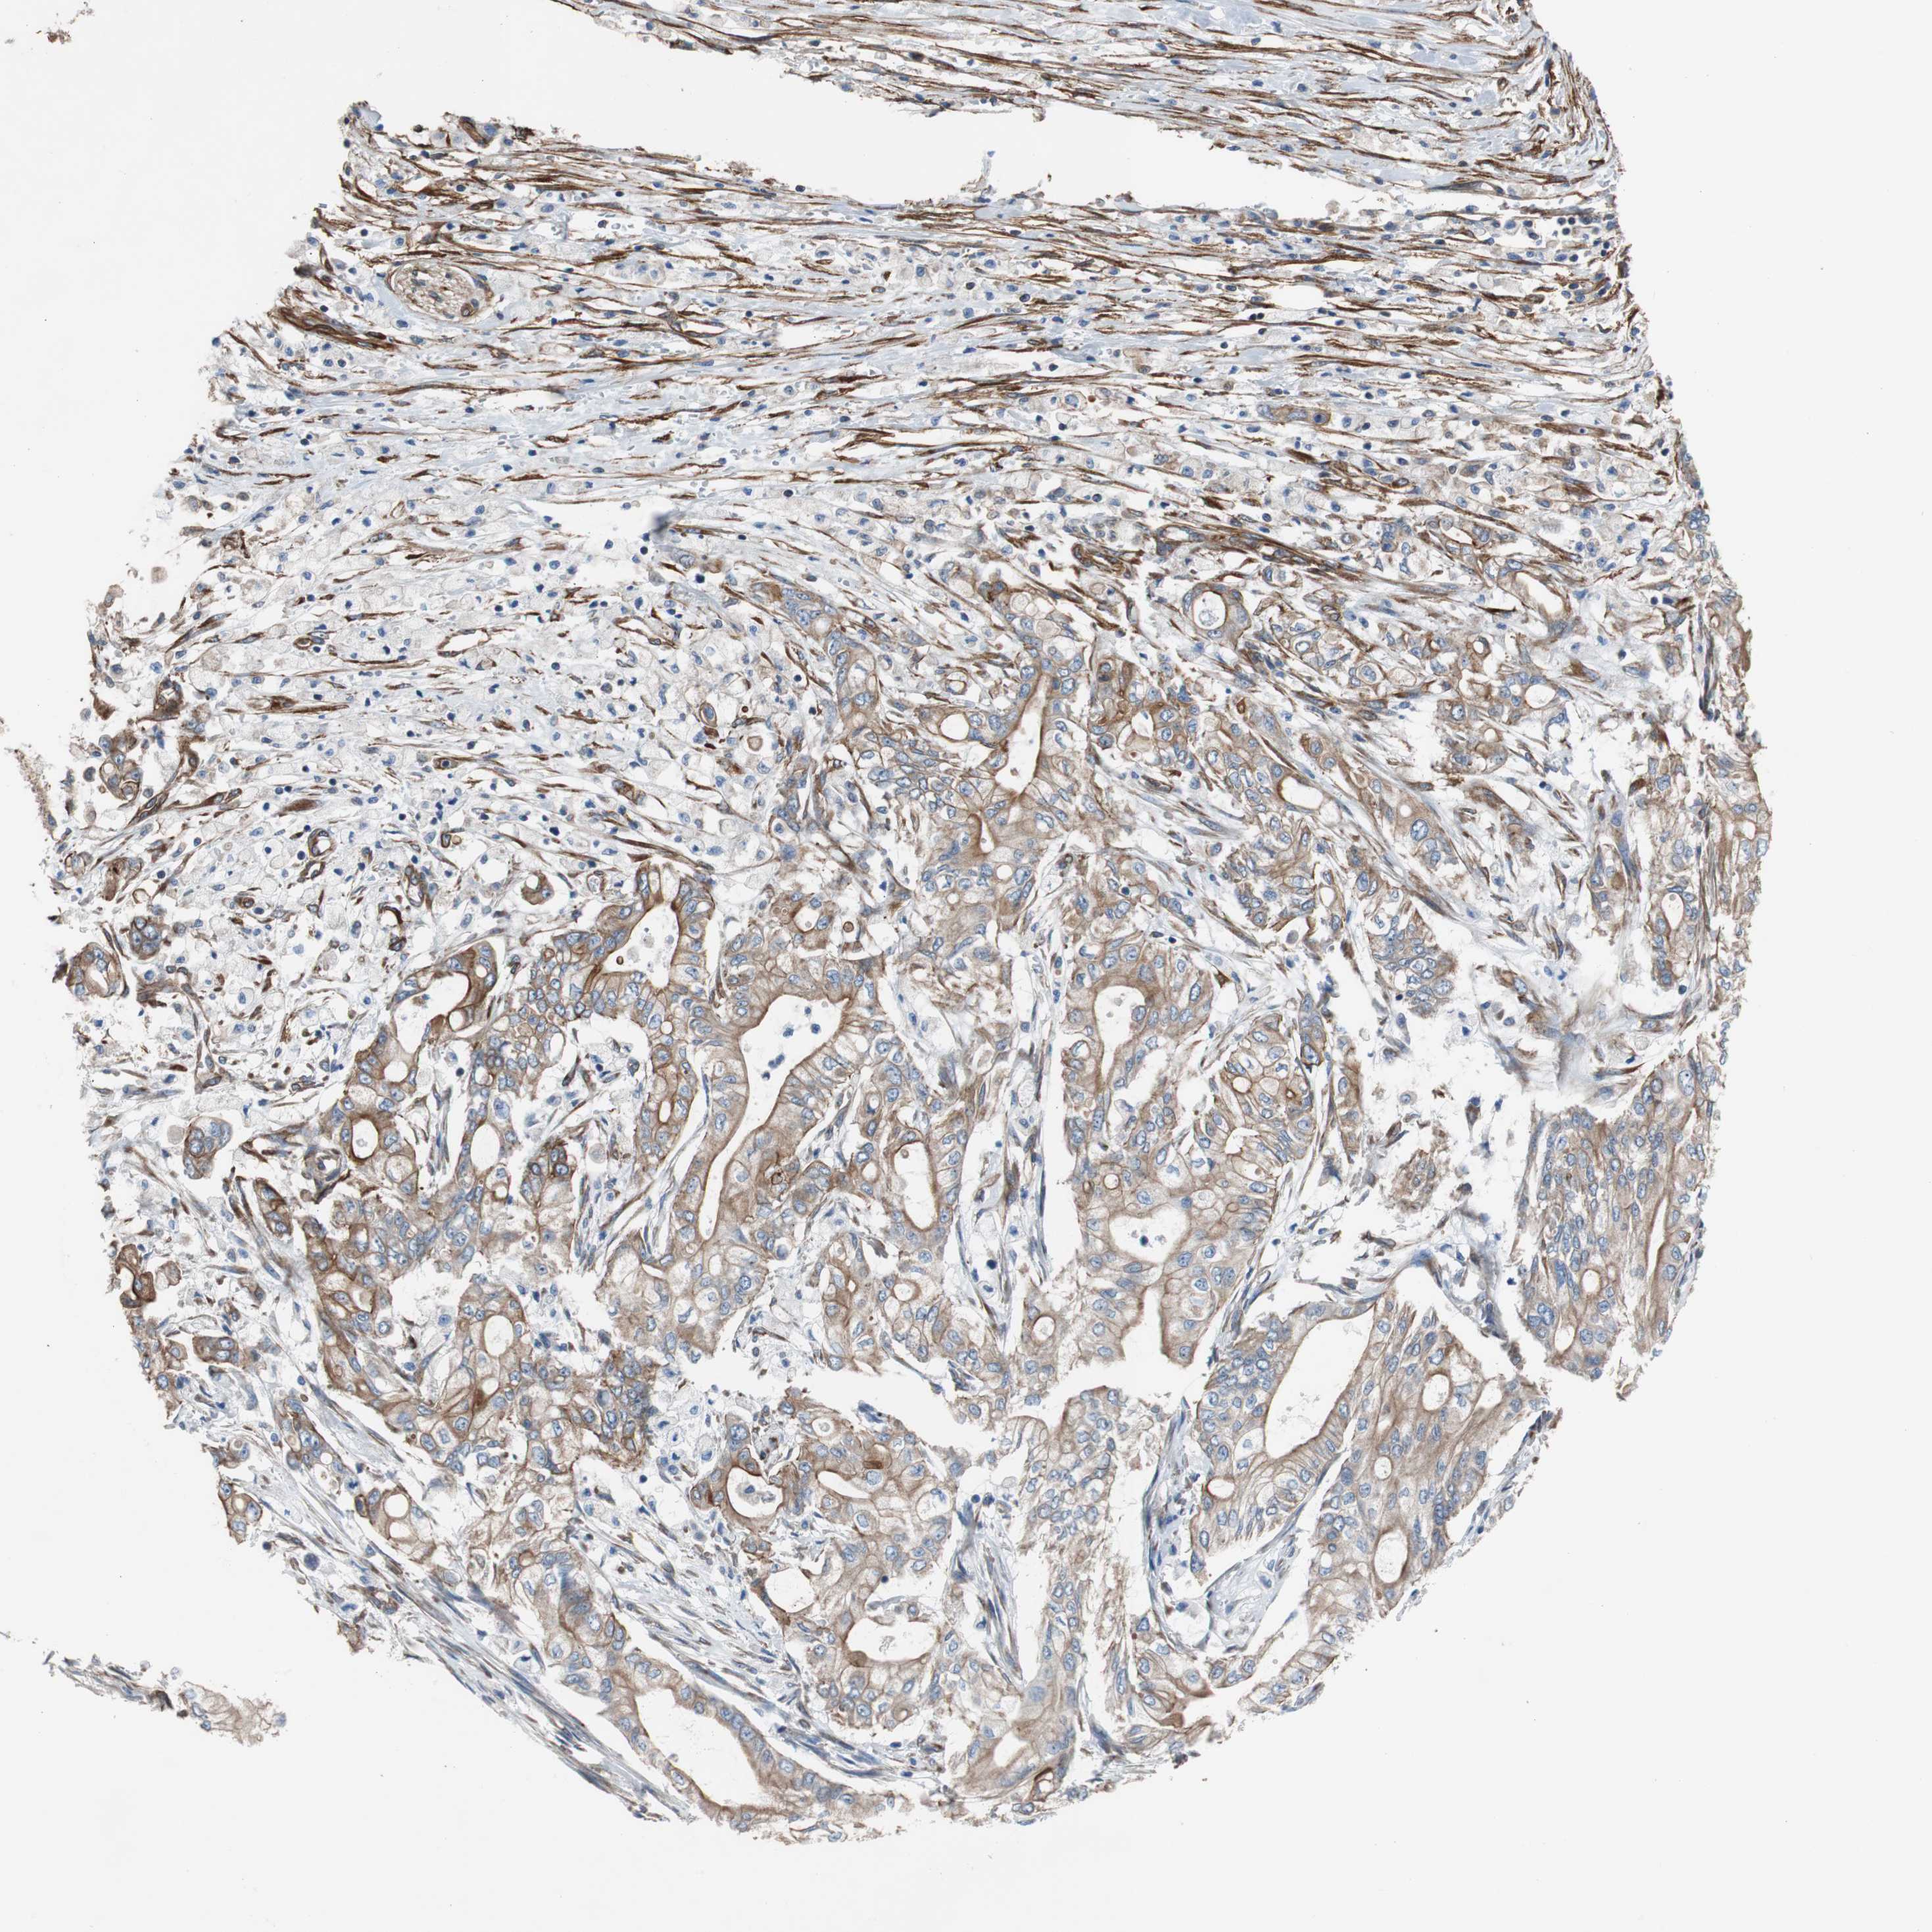

PANCREATIC CANCER - Protein expressioni

A mouse-over function shows sample information and annotation data. Click on an image to view it in a full screen mode. Samples can be filtered based on level of antibody staining by selecting one or several of the following categories: high, medium, low and not detected. The assay and annotation is described here.

Note that samples used for immunohistochemistry by the Human Protein Atlas do not correspond to samples in the TCGA dataset.

Antibody stainingi

Antibody staining in the annotated cell types in the current human tissue is reported as not detected, low, medium, or high, based on conventional immunohistochemistry profiling in selected tissues. This score is based on the combination of the staining intensity and fraction of stained cells.

Each image is clickable and will lead to virtual microscopy that enables deeper exploration of all samples and also displays staining intensity scores, fraction scores and subcellular localization as well as patient and tissue information for each sample.

Antibody HPA007119

Staining

High

Medium

Low

Not detected

Intensity

Strong

Moderate

Weak

Negative

Quantity

>75%

75%-25%

<25%

None

Location

Nuclear

Cytoplasmic/membranous

Cytoplasmic/membranous,nuclear

Adenocarcinoma, NOS

Adenocarcinoma, metastatic, NOS